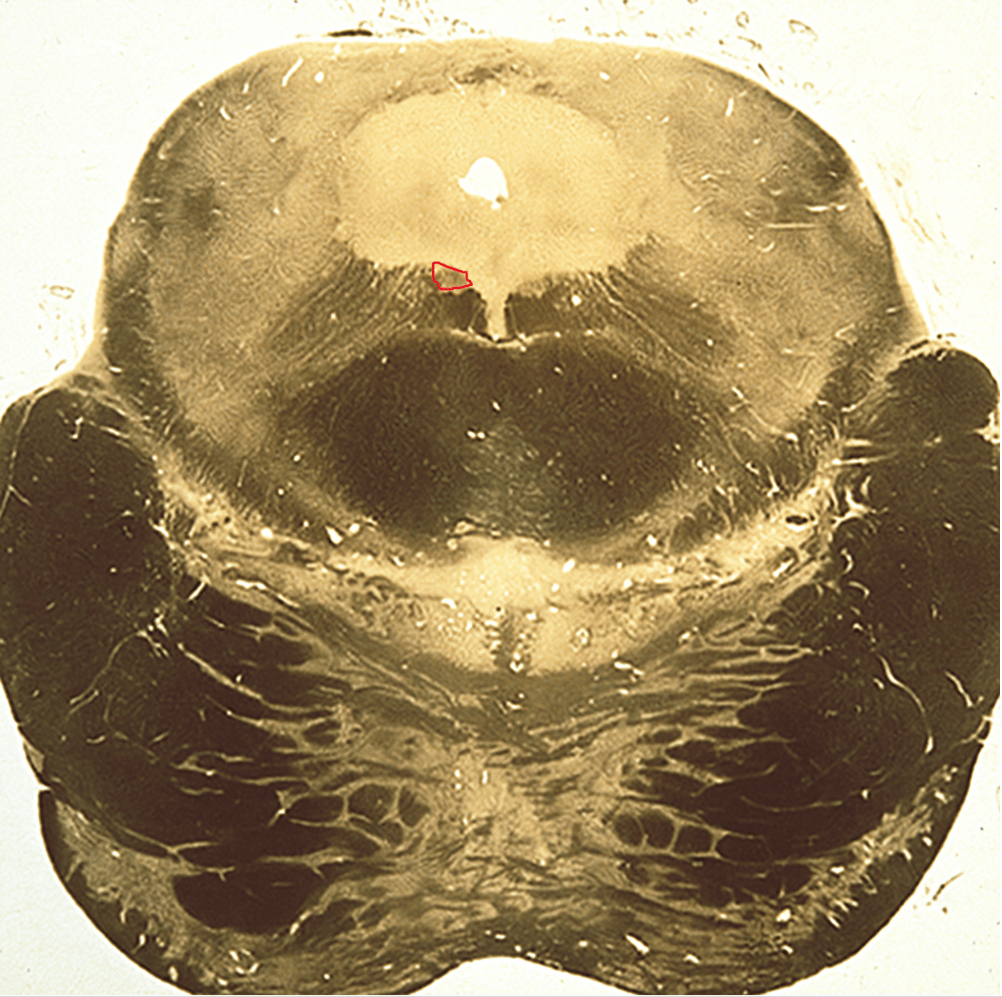

Identify the cranial nerve that originates from the circled nucleus and state whether a lesion of the nucleus would produce a contralateral or ipsilateral deficit.

Answers: Trochlear nerve and contralateral deficit

Most cranial nerve nuclei act ipsilaterally, but the trochlear nucleus is unique in that its fibers decussate within the midbrain, producing a contralateral deficit when the nucleus is damaged and an ipsilateral one when the nerve itself is damaged.